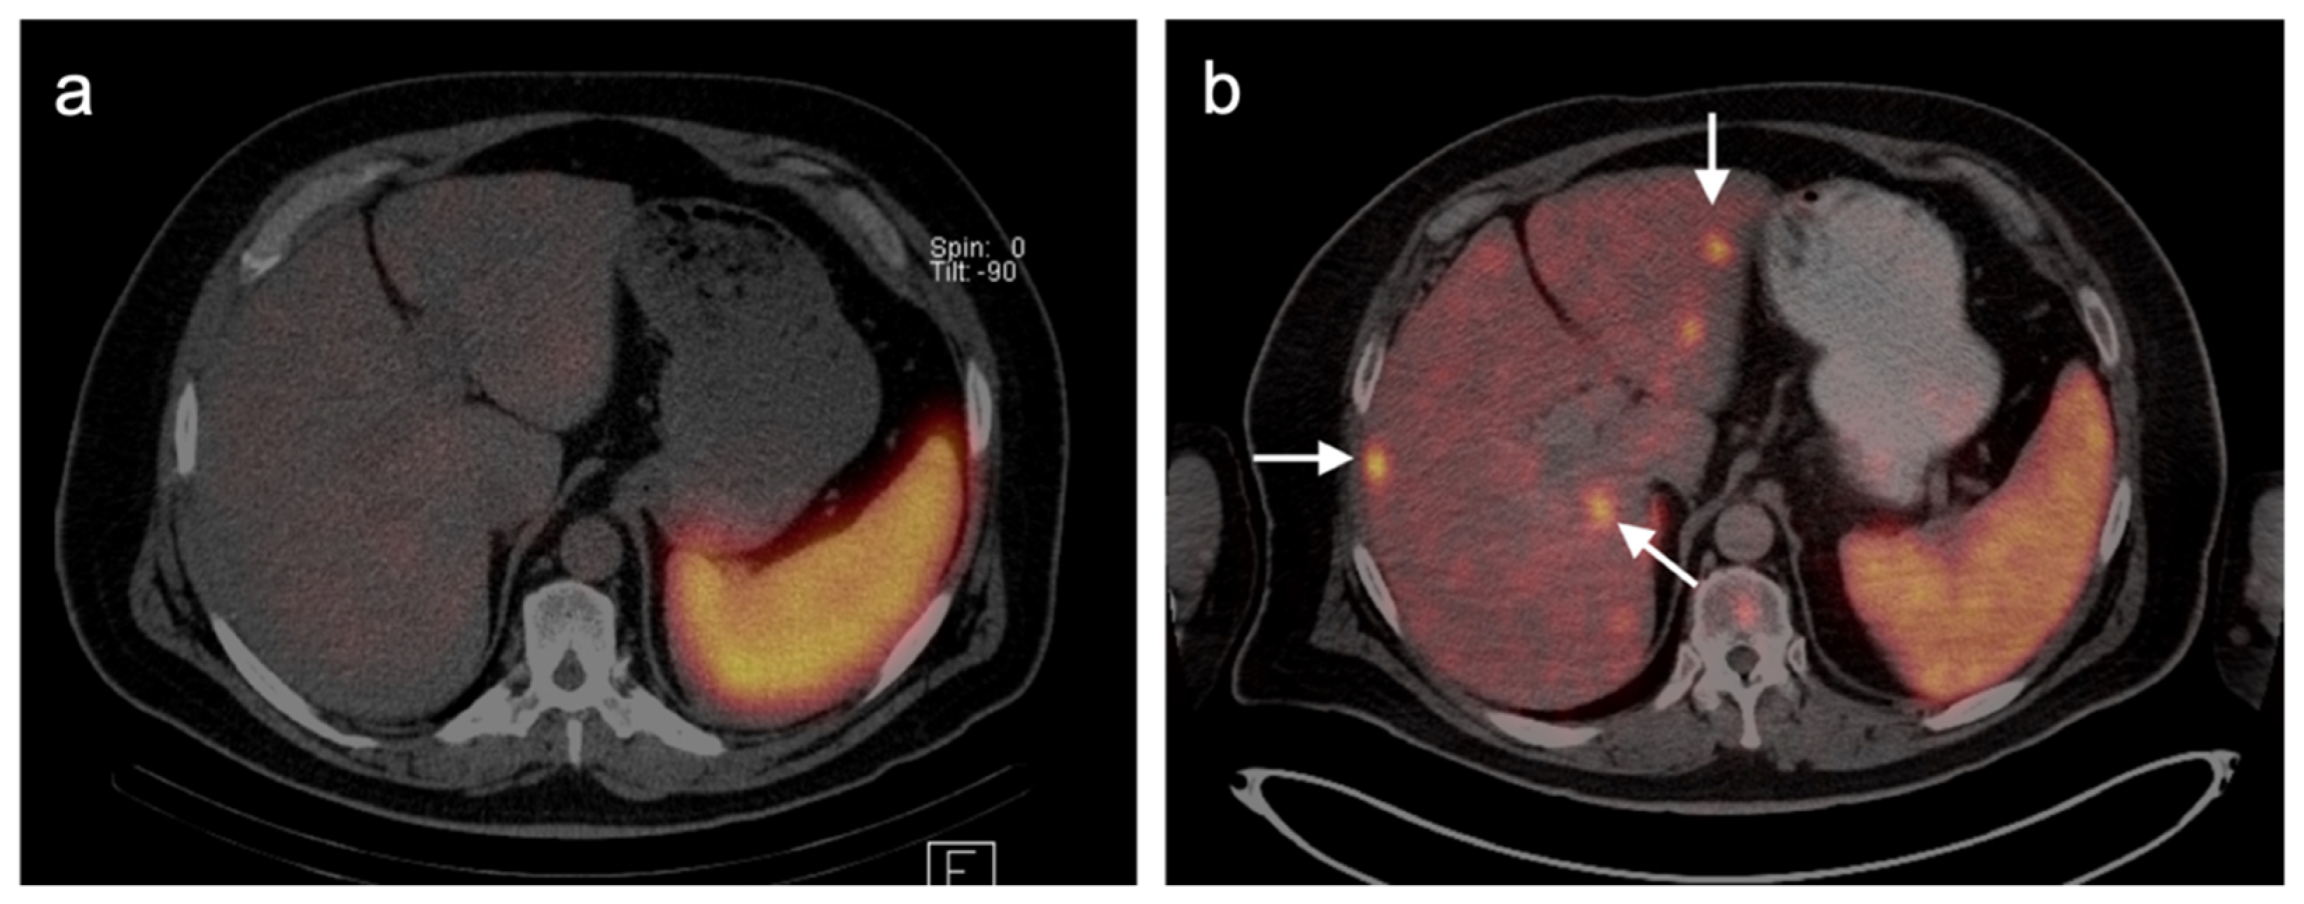

4.3. Gastroenteropancreatic (GEP) Neuroendocrine Tumors

4.4. Bronchial Carcinoid

- Webb, H.R.; Latifi, H.R.; Griffeth, L.K. Utility of whole-body (head-to-toe) PET/CT in the evaluation of melanoma and sarcoma patients. Nucl. Med. Commun. 2018, 39, 68–73. [Google Scholar] [CrossRef]